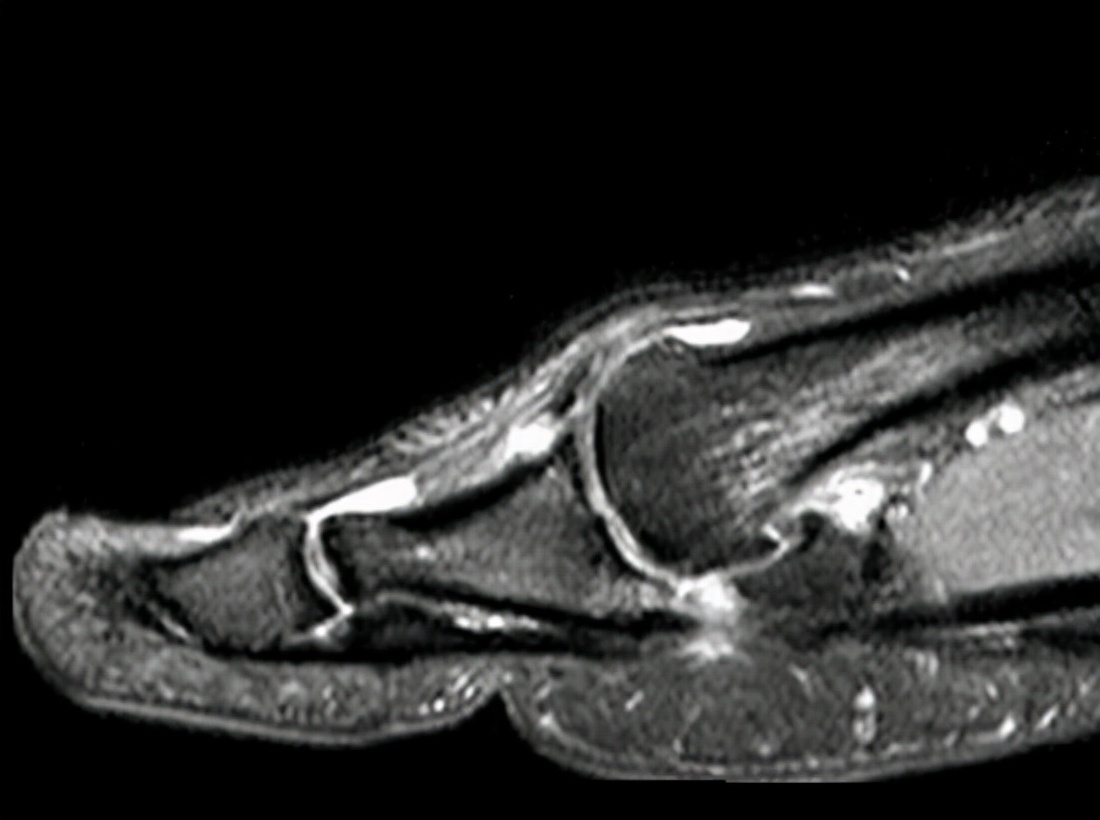

草地趾的主要症状是大拇指与脚掌相连部位附近的局部疼痛、肿胀、淤斑和肌紧张,在行走时出现疼痛步态(无意识地避免大拇趾负重)。可通过核磁共振等影像学方面的检查来确定关节囊附近的软组织损伤,并排除籽骨、关节面、跖骨、腱鞘等其他类型的病变和损伤。如果只是单纯的第一跖趾关节软组织扭伤(草地趾),则可在急性症状期采用休息、冰敷、加压包扎、抬高患肢的手段缓解疼痛和肿胀,当急性症状得控制后,可在保护装置(例如:行走靴、硬底鞋、拇趾人字绷带)的辅助下逐步恢复到日常活动和体育活动。但如果是其他疾病引发的症状,则要根据情况考虑实施不同的治疗方案。介于此,应将草地趾与下列症状相近的疾病进行区分。

1、拇趾骨折、脱位。可通过影像学证据加以排查(例如:通过X光线、骨扫描、CT、MRI等手段找到显著证据)。2、拇趾僵硬、跖趾关节炎。多与骨刺、骨赘、组织纤维化等慢性病变有关,一般都不是急性疾症;可通过影像学证据加以排查。3、籽骨损伤。压痛点更加集中于籽骨,范围更小。可通过影像学证据加以排查。4、籽骨疲劳骨折。压痛点更加集中于籽骨,范围更小;慢性疾症;可通过影像学证据加以排查。5、二分籽骨。籽骨因先天未融合而出现裂痕,影像学检查可见籽骨中间的低密度线(非骨折线);无压痛;双侧同时发生的概率较大。6、籽骨关节炎。压痛点更加集中于籽骨,范围更小;活动时疼痛加重;可通过影像学证据加以排查。